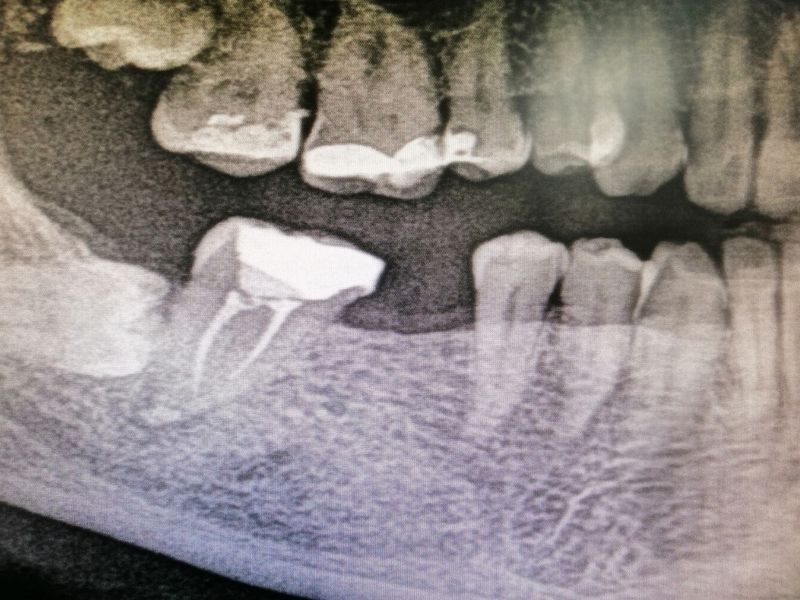

Finalmente, con todo listo para reponer las piezas dentales ausentes, se procede a la preparación de todo el instrumental técnico necesario y a realizar la cirugía de colocación de los implantes. Paso a paso, un poco más cerca de finalizar el tratamiento y devolver al paciente a su mejor estado de salud bucodental.